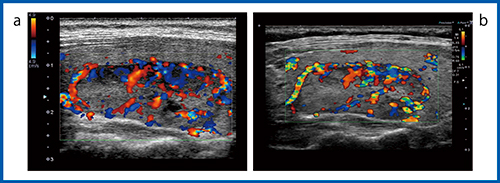

2)カラードプラ法

カラードプラ法の甲状腺の画像を供覧する。図4は正常な甲状腺のパワードプラ画像だが,Aplio XG(b)では深部の太い血管はよくわかるが,体表に近い部分は血流か,アーチファクトかの判断が難しい。Aplio 500(c)では体表に近い部分は血流であることはわかるものの,血管外へのはみ出し(ブルーミング)が強く血管像がぼやけて見える。Aplio i800(a)では,アーチファクトが減り細かい血流が明瞭に描出されている。充実性腫瘍の画像(図5)でも,全体の血流が描出されており,特にAplio i800(b)ではブルーミングが抑えられ細かい血流まで確認できる。また,カラードプラ法(CDI:図6)では,同様にAplio i800(b)の方が細かい血流まできれいに描出されている。

図4 超音波診断装置の進化:パワードプラ法(12MHz)

a:Aplio i800 b:Aplio XG c:Aplio 500

図5 パワードプラ法による充実性腫瘍の描出能の比較(12MHz)

a:Aplio 500 b:Aplio i800

図6 超音波診断装置の進化:カラードプラ法